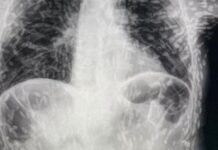

Tenya’ların bu kadar saldırgan olduğunu kim tahmin ederdi! Organları deldi geçti, beyne yumurtalarını bıraktı!

Brezilyalı doktorlar, kendilerini şaşırtan bir vakanın röntgen görüntülerini paylaştı. İyileşmeyen öksürük...